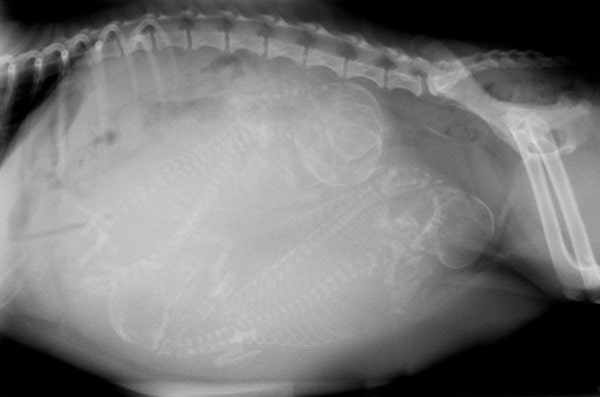

Рентген

Рентгенівський знімок — ефективний засіб для визначення вагітності собаки. Потрібно врахувати, що рентген роблять тоді, коли скелети цуценят уже оформилися — приблизно з 42-45 і до 55 дня вагітності суки. На рентгенівському знімку в цей час видно точну кількість цуценят. Такий спосіб дає максимальну інформацію про вагітність вихованця і дозволяє краще підготуватися до майбутніх пологів.

Виношування цуценят у собак відносно короткий час, вагітність триває близько 9 тижнів. Кожен день має значення. Знання тривалості періоду вагітності важливе для здоров’я вагітної суки та цуценят. Плід починає формуватися до 22 дня. На 28-30 день можна почути серцебиття цуценяти. У другому місяці плід швидко розвивається: до 32 дня формуються повіки, кігті — до 40 дня, на 45 день формується скелет. До 50-го дня рентген покаже кількість цуценят у посліді.